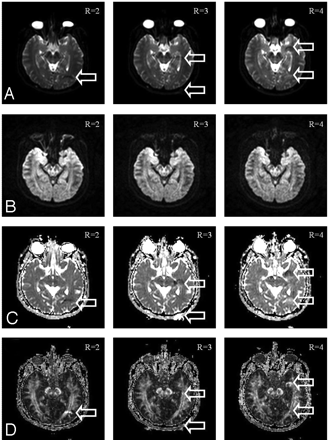

The b = 0 SENSE-EPI images with bright eyeball signal intensity and serious distortion suffered from unfolding artifacts, as shown in Fig 3. The susceptibility-induced, ghost-like artifacts showed spatial displacements consistent with the unfolding artifacts in parallel imaging at FOV/R along the phase-encoding direction, where R was the acceleration factor (Fig. 3, top row, arrows). However, in the high b-value (1000 s/mm2) diffusion-weighted images, the unfolding artifact was visually absent (Fig. 3, second row) because the diffusion-sensitizing gradient attenuated the eyeball signal intensity. Consequently, the DTI image reconstruction with use of the artifact-contaminated b = 0 and 6 artifact-free b = 1000 images gave rise to the ADC and FA maps showing pseudolesions (arrows in third and bottom rows of Fig. 3, respectively). With a saturation band placed over the eyeball region, signal intensity from the distorted eyeball images became saturated. Therefore, no unfolding artifact was present in the b = 0 and b = 1000 images (Fig. 4, two top rows). Therefore, the pseudolesions were removed in the calculated ADC and FA maps (Fig. 4, two bottom rows).

The b = 0 images (top row) acquired with SENSE parallel imaging at acceleration factors of R = 2, 3, and 4 (left to right columns, respectively) show ghosting from the eyeballs, displaced spatially along the phase-encoding direction at FOV/R, consistent with SENSE unfolding artifacts (first row; arrows). The corresponding b = 1000 diffusion-weighted images exhibit no artifacts (second row), hence resulting in pseudolesion intensity in the ADC and FA maps mimicking diffusion abnormality (third and bottom rows, respectively; arrows).

In the same arrangement as Fig. 3, the b = 0 and b = 1000 images, and the ADC and FA maps (top to bottom rows, respectively) obtained with the saturation band to suppress the eyeball signals show no pseudolesions.